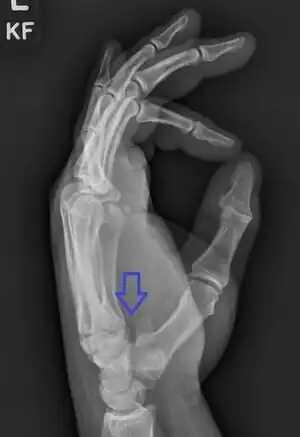

Hamate fracture is a break of the hamate bone in the wrist. Symptoms include pain in the front of the wrist in line with the little finger.[1] It is made worse by gripping an object.[1] Complications may include injury to the ulnar nerve and clotting of the ulnar artery.[1]

The cause is typically injury during racket sports, baseball, or golf or a fall onto the hand.[1][2] Types include hook (most common) and body (proximal pole, medial tuberosity, sagittal oblique, and dorsal coronal).[1] Diagnosis is typically by X-rays, but may require special views such as a carpal tunnel or supinated oblique view; or a CT scan.[1]